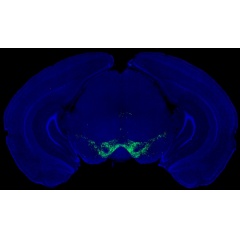

Image by Nicolas Tritsch [Fluorescence microscopy image of dopamine-producing neurons (green) in the midbrain of a mouse].

A McGill-led study is challenging a popular theory about how dopamine drives movement, a discovery that could shift how scientists think about Parkinson’s disease treatments.